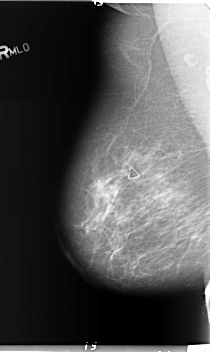

B_3152_1.RIGHT_MLO

RIGHT_CC LINES 5976 PIXELS_PER_LINE 3528 BITS_PER_PIXEL 12 RESOLUTION 50 NON_OVERLAY

RIGHT_MLO LINES 5976 PIXELS_PER_LINE 3560 BITS_PER_PIXEL 12 RESOLUTION 50 NON_OVERLAY